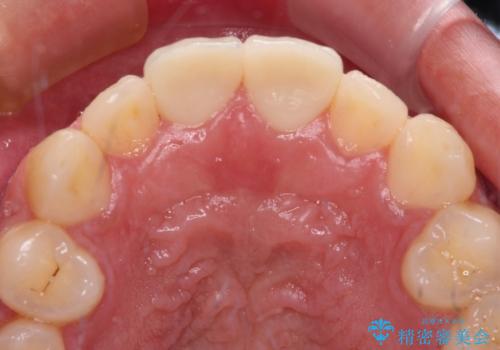

しかしながら、補綴治療後間もなく再度自転車事故に遭い、追加1本の計3本を損傷する事態となりました。

再度損傷した3本は完全に失活した状態であったため、速やかに根管治療を行い、オールセラミッククラウンにて補綴治療を行うこととしました。